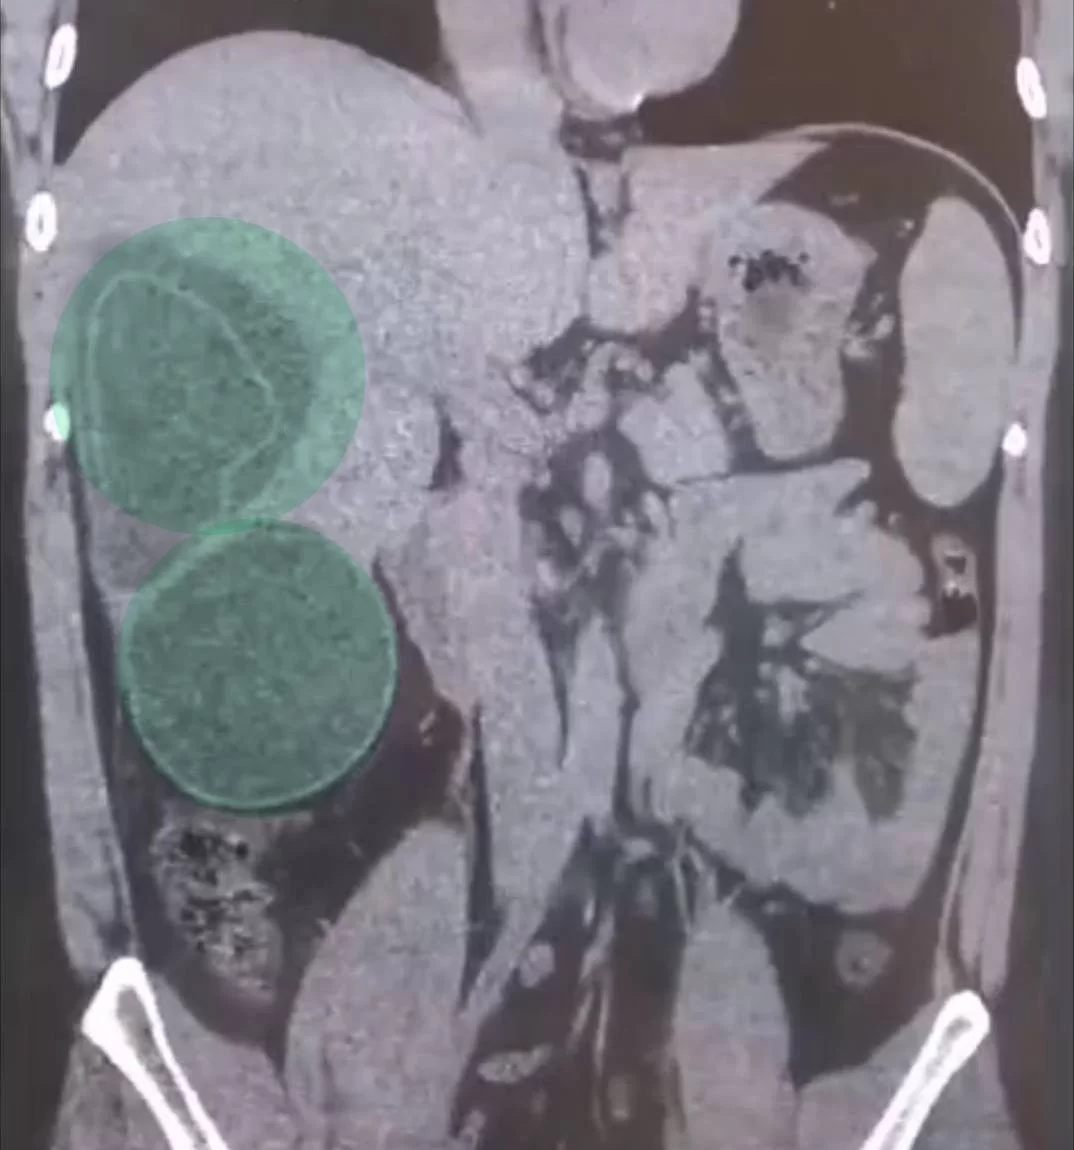

Экзотический отдых может оставить не только загар. 29-летний житель Подмосковья вернулся с Филиппин, где активно дегустировал уличную еду. Вскоре начались боли в животе и тошнота. Врачи Долгопрудненской больницы обнаружили в его печени три огромные кисты.

Это был эхинококк. Яйца паразита могли попасть в организм не столько с мясом, сколько с плохо промытой зеленью или через грязные руки после контакта с уличной пылью. Одна из кист была готова лопнуть, что привело бы к анафилактическому шоку и мгновенной смерти. Хирурги провели ювелирную работу, удаляя паразитарные капсулы, чтобы не допустить разлива смертоносной жидкости.